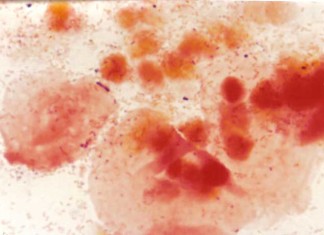

La vaginosis bacteriana se asocia con mayor riesgo de transmisión del...

Una investigación dirigida por la UCSF se ha encontrado que el riesgo de la transmisión del VIH triplicó en las mujeres con vaginosis bacteriana,...